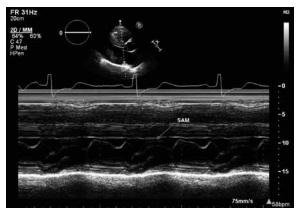

Um paciente de 41 anos de idade, hipertenso, em uso de losartana, com queixa de dispneia durante os esforços e desconforto precordial inespecífico nas últimas semanas. Seguem imagens do ecocardiograma a seguir.

Com base nessa situação hipotética e nas imagens acima, assinale a alternativa que apresenta a etiologia adequada do quadro.